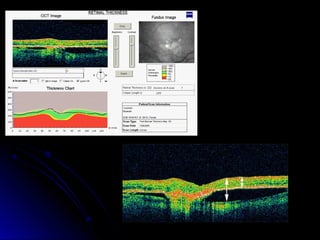

Retinal Thickness Analysis

Using the retinal thickness analysis tool, the

software then traces a line along the NFL

layer and a line along the RPE layer.

The software then measures the distance

between the two lines and a graph is

produced which compares the measured

thickness to the thickness of a normal

retina

Retinal thickness analysis does not measure

retinal elevation

for example this eye with a pigment epithelial

detachment (PED) pictured below. The arrow

on the left would represent retinal elevation,

from the choroid, through the fluid space of the

PED, to the nerve fiber level. The arrow on the

right shows what the analysis measures, defined

by the distance from the RPE (which is

detached) to the NFL